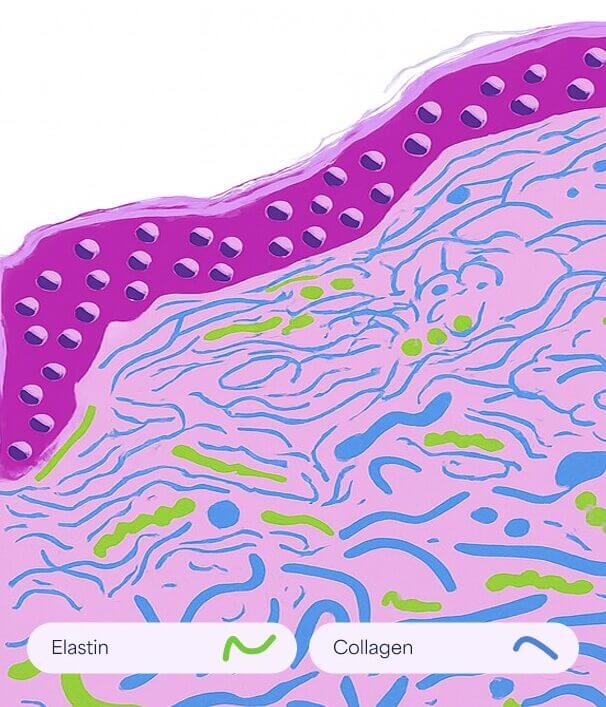

Dehnungsstreifen

Normale Haut

Glatt und elastisch, wobei intakte Kollagen- und Elastinfasern für Festigkeit und Struktur sorgen.

Striae Rubrae

Glatt und elastisch, wobei intakte Kollagen- und Elastinfasern für Festigkeit und Struktur sorgen.

Striae Albae

Reife weiße Dehnungsstreifen, bei denen die Umstrukturierung des Kollagens zu einer Ausdünnung und einem Verlust der Pigmentierung führt.

So funktioniert es

- Fördert den Abbau von geschädigtem Kollagen

- Es induziert die Proliferation von Keratinozyten, die Wachstumsfaktoren freisetzen, um die Kollagenablagerung durch Fibroblasten und die Elastinablagerung zu fördern.

- Moduliert die Expression mehrerer Gene in der Haut (vaskulärer endothelialer Wachstumsfaktor, Fibroblasten-Wachstumsfaktor, epidermaler Wachstumsfaktor, Kollagen Typ I und III), die die Umgestaltung der extrazellulären Matrix fördern.